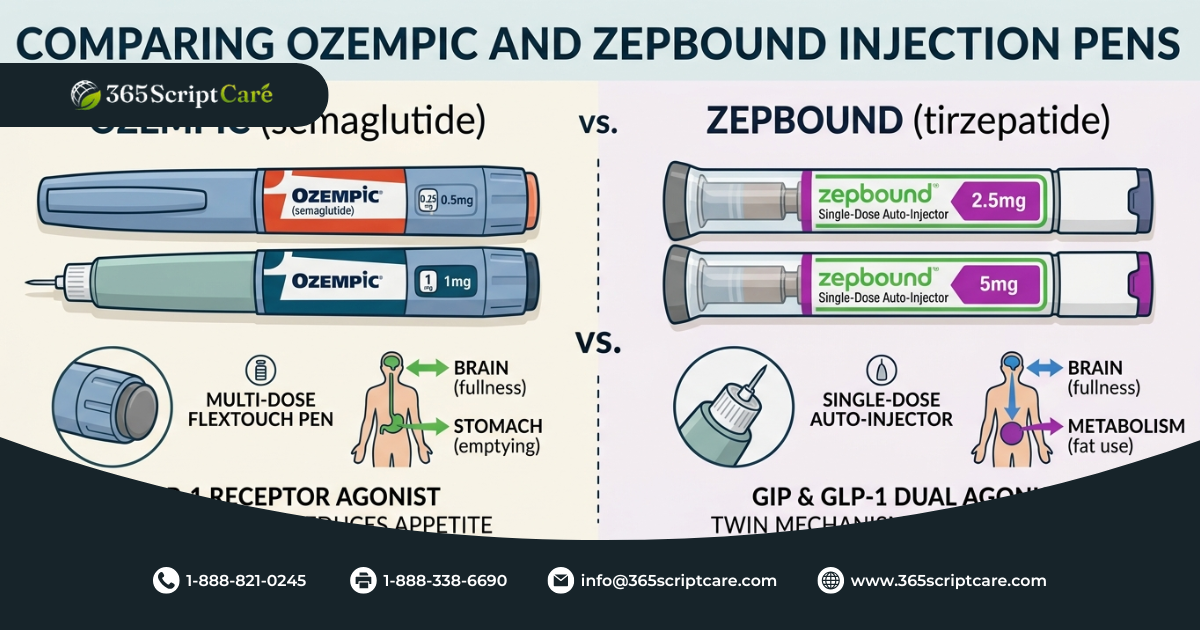

Want to compare weight loss medications? Our article on how Zepbound works for weight loss breaks down how a similar treatment approach compares to Ozempic doses.

How Do Ozempic Doses Compare to Similar Medications?

Mounjaro (Tirzepatide) starts at 2.5 mg and reaches up to 15 mg, giving it a much wider dose range than Ozempic doses. It also targets two hormone receptors rather than one, which contributes to stronger weight loss outcomes for some patients. Wegovy uses the same Semaglutide as Ozempic but is dosed up to 2.4 mg and approved specifically for weight management. Trulicity (Dulaglutide) is another weekly option that ranges from 0.75 mg to 4.5 mg and is approved for type 2 diabetes.